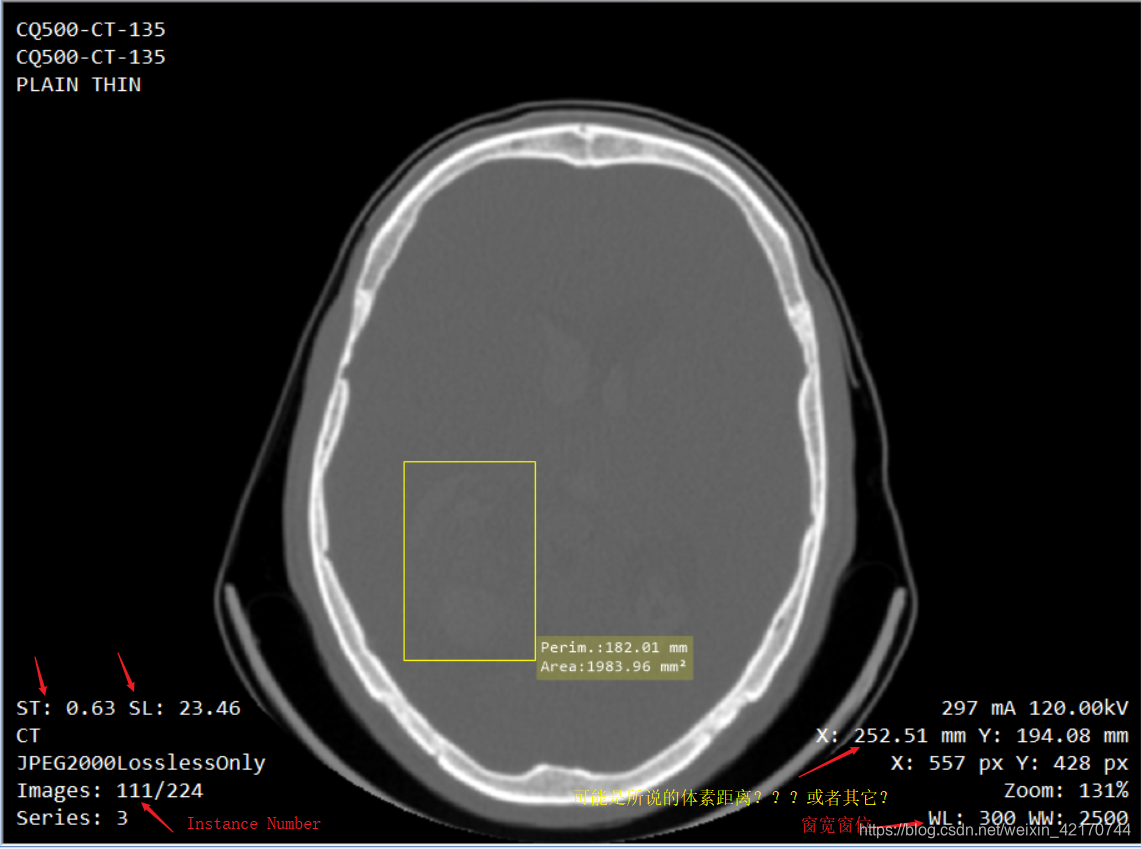

如上图标记所示,可用的也就是自适应调窗工具和滤波工具

上面的测距工具可能是针对于体素距离的,不适用于一般csv文件给的像素距离;但不知选择Plane Tool后怎么测距,即选择像素距离。

如上图标记所示,可用的也就是自适应调窗工具和滤波工具

上面的测距工具可能是针对于体素距离的,不适用于一般csv文件给的像素距离;但不知选择Plane Tool后怎么测距,即选择像素距离。